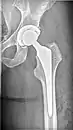

X-ray of hip with femoral head osteonecrosis

Left hip total arthroplasty

Hip replacement

When patients have later stages of ONFH most other treatment options are not successful or even worth trying. Thus the only option is total hip replacement where the FH and the pelvic portion of the joint are both replaced, or one part of the hip joint is replaced. Many surgeons do choose to just replace the hip altogether in some mild cases because hip replacements have a longer success rate and most of the time if you try to do partial replacements or FH sparing techniques that are not totally successful: later in life a hip replacement is needed. A lot is needed to take into consideration including age and progression.[3]